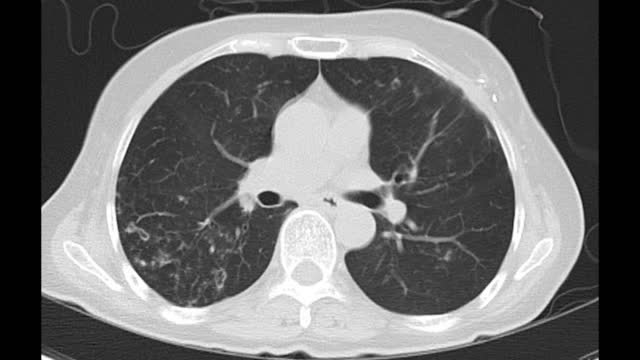

폐암은 폐에서 생기는 악성 종양으로, 결절이라고도 불립니다.

이러한 결절은 폐 내에 작은 덩어리 혹은 종양으로 나타날 수 있으며, 그 중에서도 양성과 악성 종양이 구분됩니다.

폐암은 초기에는 증상이 미미하여 진단이 어려울 수 있습니다. 주로 호흡기 증상으로 나타나며, 기침, 가래, 혈올림, 흉통, 호흡곤란 등이 그 예입니다.

초기 폐암의 경우 종양의 크기가 작아서 통증이나 불쾌한 증상이 없을 수 있으며, 종양이 기관지 주변을 침범하거나 기관지 내부에 자극을 주면서 기침과 가래가 나타날 수 있습니다.